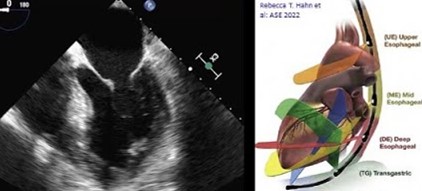

O ETE é um exame de ultrassom avançado que oferece imagens detalhadas do coração e grandes vasos através de um transdutor especial introduzido pelo esôfago. Esta localização privilegiada permite visualizar estruturas cardíacas com extraordinária clareza, superando limitações do ecocardiograma tradicional.